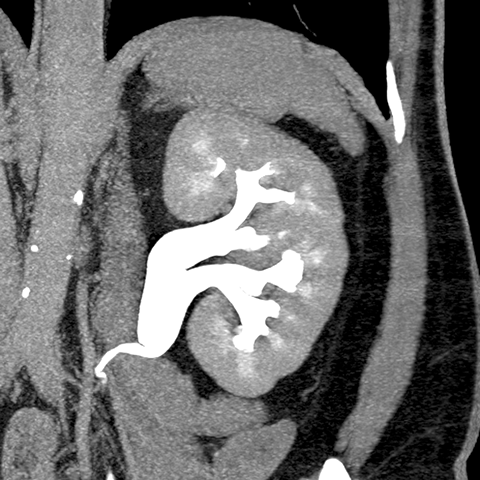

Normal kidney, CT [5 of 9]